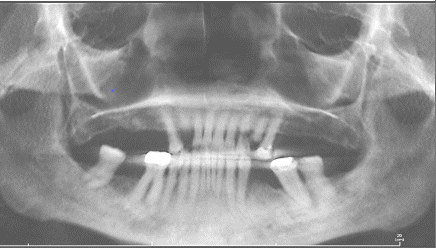

Following extraction of a lower tooth, the opposing upper tooth can move downward due to loss of support, resulting in root exposure, increased sensitivity, higher susceptibility to gum infection, and potential loosening, possibly necessitating further removal. Likewise, the posterior molar adjacent to the gap may tilt forward because of reduced lateral support. These positional changes alter bite alignment, as the upper molar may contact the edge of the affected area, potentially leading to progressive misalignment and further tooth loss. The absence of multiple teeth can affect oral structural stability and modify facial contours as lips and gums lose support.

Bone Loss

The jawbone under the gums supports tooth roots and requires stimulation to maintain its structure. Removal of a tooth causes the surrounding bone to resorb, with possible decreases of up to 25% in width within the first year and up to 4mm in height over time. This reduction can result in:

As bone deteriorates around an absent tooth and adjacent teeth shift into the space, restoring the tooth becomes increasingly difficult. Dental implants provide one solution, but they require sufficient bone quantity and quality for successful placement and integration.